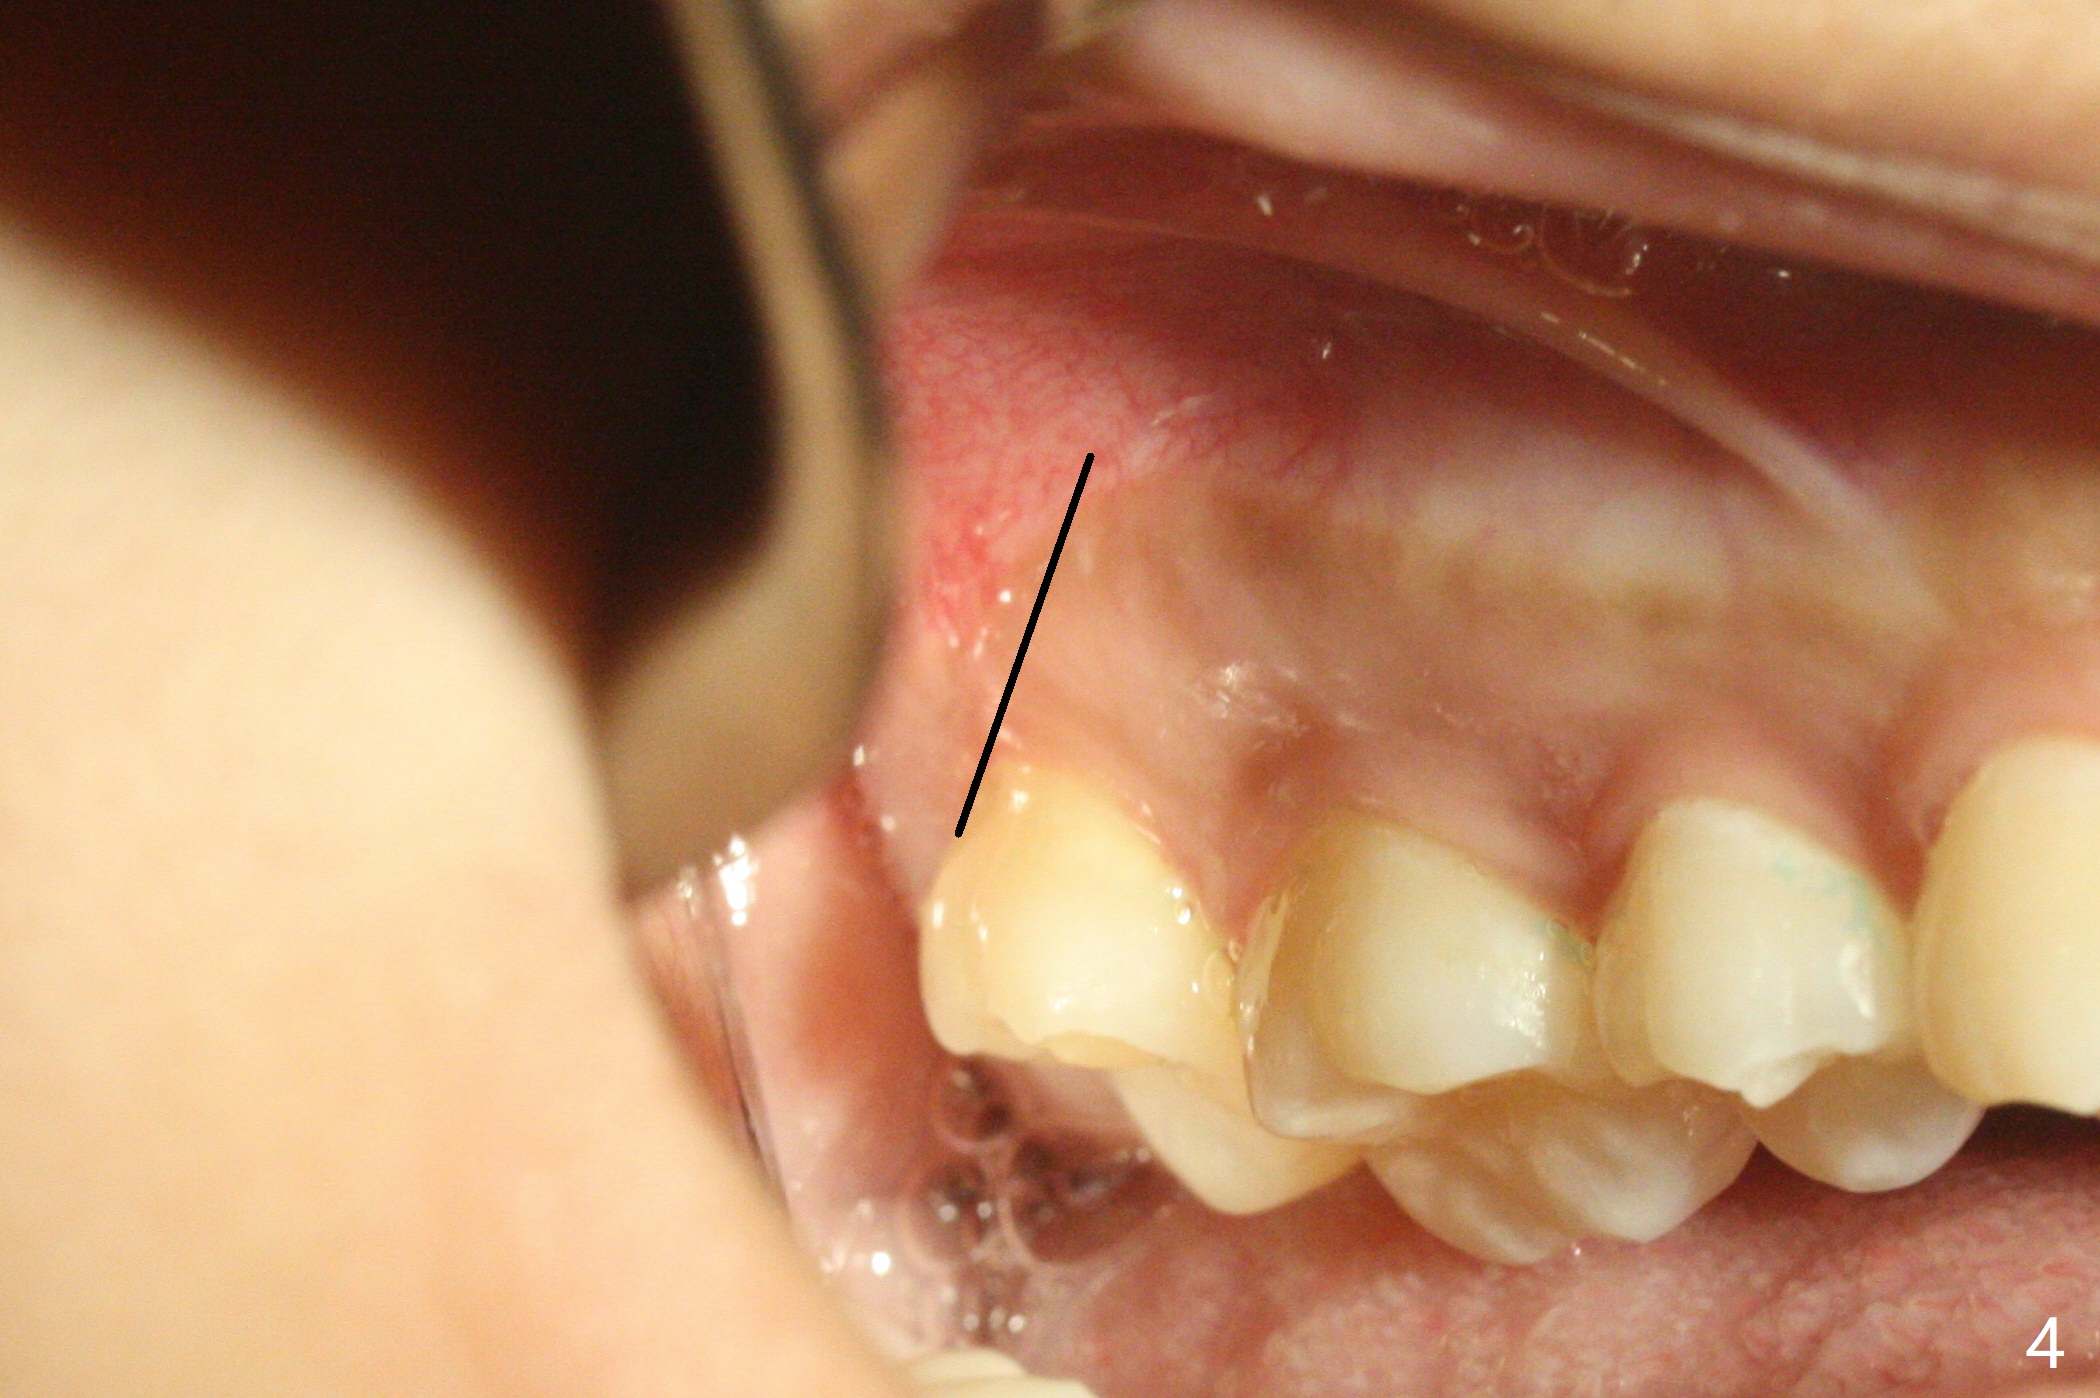

19岁女想在上大学前一次性拔除四个智齿(图一),术前口角涂抗病毒药粉(Acyclovir)凡士林(图二)。图三显示右上磨牙区,L型切口将做在第二磨牙远中(图四),光注射上牙槽后神经止痛还不够,第二磨牙上方还必须使用利多卡因(含肾上腺素1:50,000,而不是1:100,000,止血效果好)。上颌智齿区骨质松软,不必用手机钻头切骨产生purchase point,可以使用Crane Pick插入智齿近中(图五)慢慢撬动牙齿,防止大块上颌结节骨折。如果觉得杠杆作用不够,使用Potts(图六)让牙齿脱位。图七显示右下智齿区,由于舌神经位于牙槽嵴舌侧粘膜下,切口不要超过牙槽嵴(图八)。图九显示术后即刻,下颌智齿牙槽窝密度不同。原来右下牙槽窝放置骨胶原塞,而左下胶原塞。